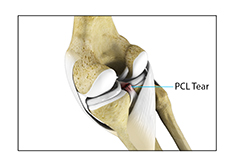

PCL Tear

Coming soon